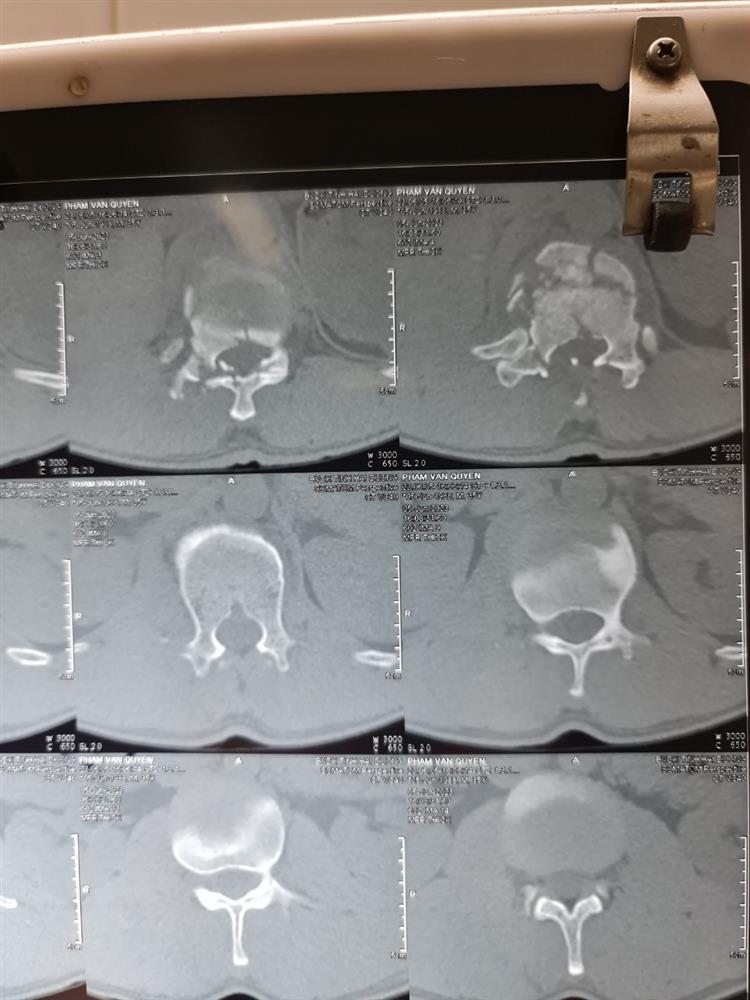

Anh Q vào viện do ngã cây vải đau nhiều cột sống thắt lưng, liệt hoàn toàn 2 chi dưới đã được các bác sĩ khoa cấp cứu BVĐK Tỉnh Hải Dương khám, cố định cột sống, chụp chiếu chẩn đoán CTCS gãy D12 L1 mất vững Frankel A , a đã được các bác sĩ hội chẩn và được các bác sĩ khoa ngoại 2 Phẫu thuật cấp cứu làm vững cột sống, giải ép tủy, khâu phục hồi màng tủy. Sau 10 ngày điều trị hiện tại sức khỏe của anh Q ổn định và được tập phục hồi chức năng, tuy đã phẫu thuật nhưng do tổn thương của anh Q phức tạp tổn thương tủy sống nên sự hồi phục vận động và cảm giác của a Q rất chậm và cần phải có một thời gian rất dài.